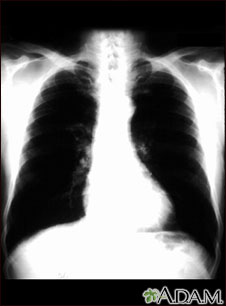

- Chest x-ray